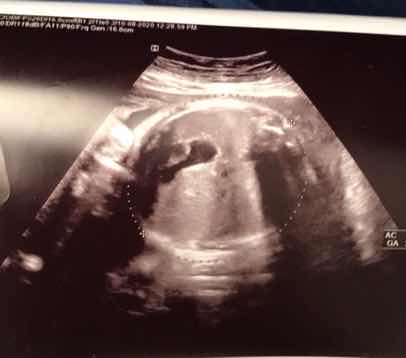

بياض امعاء الجنين هل يعني الطفل داون

مرحبا أنا حامل في الشهر الرابع كنت قد أجريت صورة سونار في الاسبوع ال ١٢ من الحمل و قالت لي...